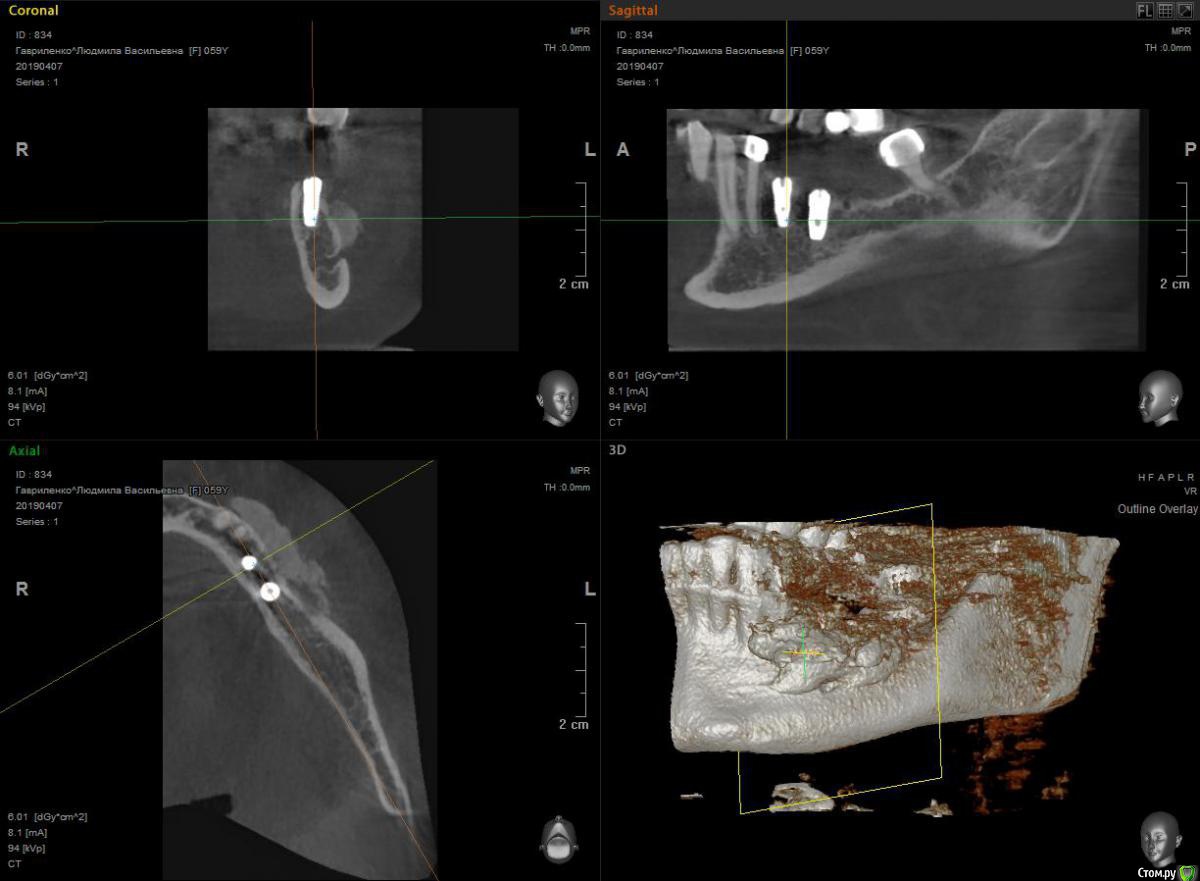

HAV Опубликовано 9 апреля, 2019 Автор Поделиться Опубликовано 9 апреля, 2019 Здравствуйте. Ситуация развивается дальше, без изменений. Сохраняется онемение нижней губы слева (на кожных покровах, ближе к краю нижней челюсти, на слизистой оболочке чувствительность сохранена), сохраняется незначительный отек в области тела нижней челюсти слева. Пациентка отмечает что каждый вечер у нее возникают болевые ощущения в области проведенной имплантации, она принимает обезболивающее, далее ничего не беспокоит. Я уже теряюсь между диагнозами - Парэстезия, Периимплантит? На КТ определяется разрежение костной ткани в области имплантата 35, но при повторении снимка на визиографе этого разрежения не наблюдается 9 может на КТ "фон", "отсвечивание" от имплантата? Вчера раскрыл рану, попытался убрать часть костного материала из области ментального отверстия, пока все без изменений. Хотелось бы услышать совет. Спасибо. Ссылка на комментарий

Дмитрий М Опубликовано 9 апреля, 2019 Поделиться Опубликовано 9 апреля, 2019 Здравствуйте. Ситуация развивается дальше, без изменений. Сохраняется онемение нижней губы слева (на кожных покровах, ближе к краю нижней челюсти, на слизистой оболочке чувствительность сохранена), сохраняется незначительный отек в области тела нижней челюсти слева. Пациентка отмечает что каждый вечер у нее возникают болевые ощущения в области проведенной имплантации, она принимает обезболивающее, далее ничего не беспокоит. Я уже теряюсь между диагнозами - Парэстезия, Периимплантит? На КТ определяется разрежение костной ткани в области имплантата 35, но при повторении снимка на визиографе этого разрежения не наблюдается 9 может на КТ "фон", "отсвечивание" от имплантата? Вчера раскрыл рану, попытался убрать часть костного материала из области ментального отверстия, пока все без изменений. Хотелось бы услышать совет. Спасибо. плохо зафиксировали мембрану, по снимку графт мигрировал (сполз) 2 Ссылка на комментарий

Smileee Опубликовано 9 апреля, 2019 Поделиться Опубликовано 9 апреля, 2019 Тоже склоняюсь к тому, что графт давит на нерв. Ссылка на комментарий

HAV Опубликовано 9 апреля, 2019 Автор Поделиться Опубликовано 9 апреля, 2019 Да, полностью согласен, для этого и выполнял повторное вмешательство. Надеюсь парестезия временная т.к. просвет канала не перекрыт, и чувствительность нарушена лишь частично. Конечно, все - результат снабжения клиники ( нет пинов, нет винтов, покупают все неохотно!). Ну. а как насчет "разрежения костной ткани вокруг имплантата, периимплантит? Ссылка на комментарий

Дмитрий Л. Опубликовано 9 апреля, 2019 Поделиться Опубликовано 9 апреля, 2019 Дмитрий М на картинке все верно показал. Я бы убрал всё это, толку от него ноль. После интеграции можно будет провести новую аугментацию с сеточкой, прикреалённой к имплантату, ну или птфе мембраной с титановым каркасом. Хотя трудно будет объяснить необходимость повторных вмешательств. По Кт имплантат не прикрыт костью с одной стороны, а что по факту? Ссылка на комментарий